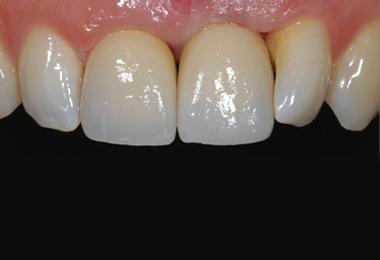

Comparable à une racine artificielle, l’implant dentaire est un petit objet cylindrique de la forme d’une vis qu’un chirurgien-dentiste fixe dans l’os maxillaire du patient. Deux a trois mois sont nécessaires à son intégration osseuse. Il remplace la racine de la dent perdue qui offre ainsi une base robuste pour accueillir une couronne, un bridge ou une prothèse dentaire amovible, et permettre au patient de mastiquer normalement et sans encombres.

Le recours aux implants permet de restituer mastication, équilibre, parole et sourire. Un implant posé dans de bonnes conditions et entretenu peut fonctionner toute une vie, avec la nécessité de renouveler uniquement la prothèse adaptée.